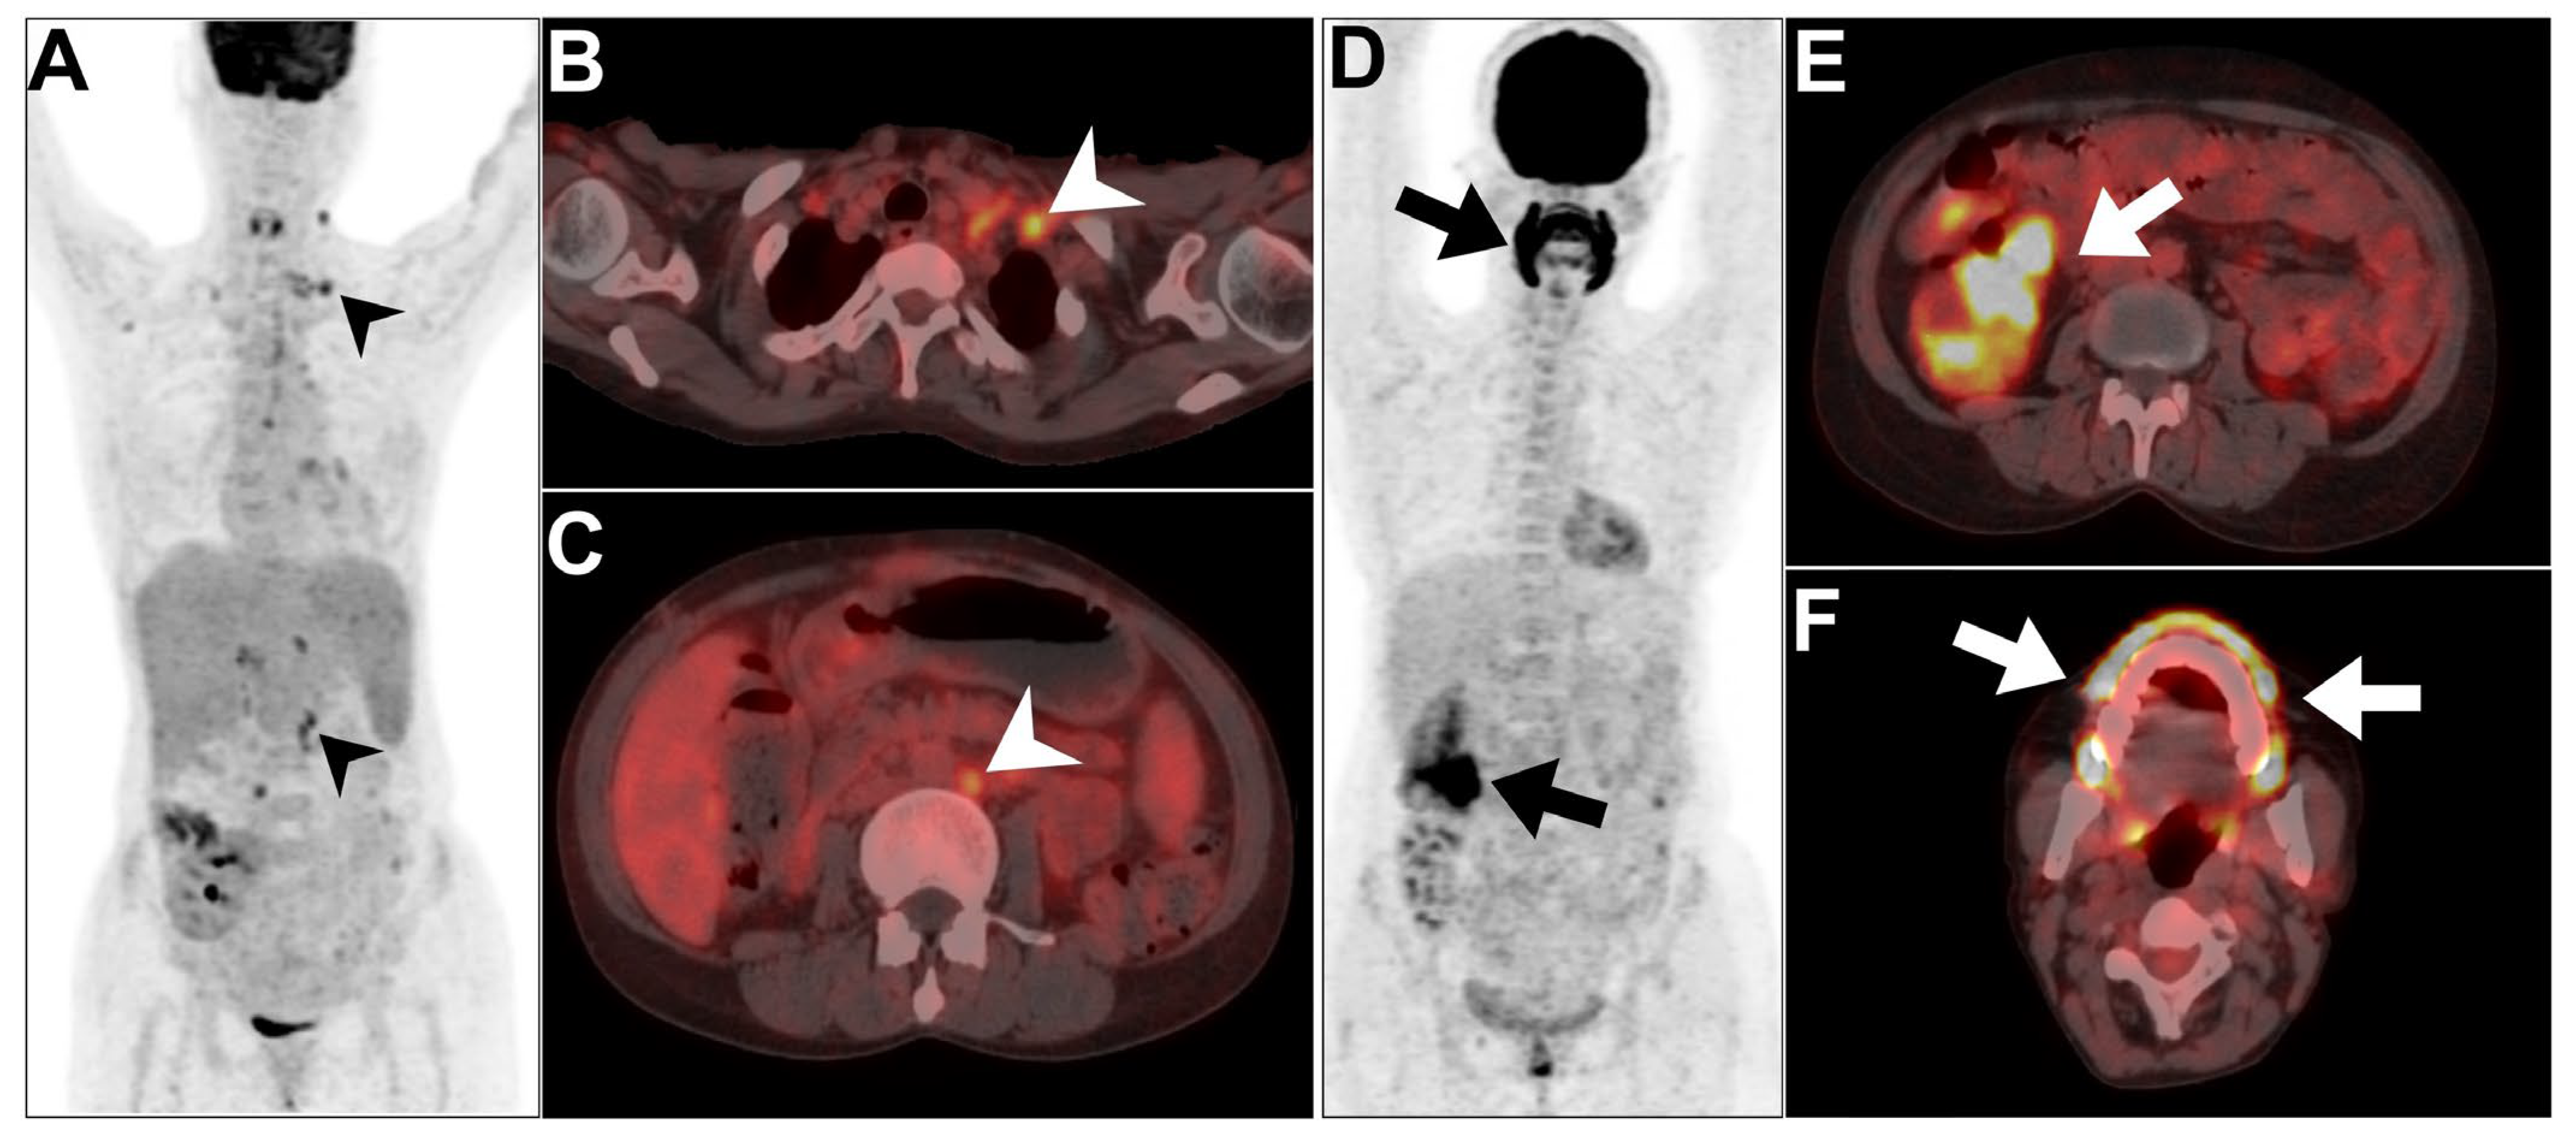

- Lovinfosse, P.; Weekers, L.; Bonvoisin, C.; Bovy, C.; Grosch, S.; Krzesinski, J.-M.; Hustinx, R.; Jouret, F. Fluorodeoxyglucose F18 positron emission tomography coupled with computed tomography in suspected acute renal allograft rejection. Am. J. Transplant. 2016, 16, 310–316. [Google Scholar] [CrossRef] [PubMed]

- Hanssen, O.; Weekers, L.; Lovinfosse, P.; Jadoul, A.; Bonvoisin, C.; Bouquegneau, A.; Grosch, S.; Huynen, A.; Anglicheau, D.; Hustinx, R. Diagnostic yield of 18F-FDG PET/CT imaging and urinary CXCL9/creatinine levels in kidney allograft subclinical rejection. Am. J. Transplant. 2020, 20, 1402–1409. [Google Scholar] [CrossRef] [PubMed]

- Pan, B.; Zhu, X. 18F-FDG PET/CT imaging of posttransplant lymphoproliferative disorder following renal transplantation: Three clinical cases. Heliyon 2023, 9, e14746. [Google Scholar] [CrossRef]

- Derlin, T.; Gueler, F.; Bräsen, J.H.; Schmitz, J.; Hartung, D.; Herrmann, T.R.; Ross, T.L.; Wacker, F.; Wester, H.-J.; Hiss, M. Integrating MRI and chemokine receptor CXCR4-targeted PET for detection of leukocyte infiltration in complicated urinary tract infections after kidney transplantation. J. Nucl. Med. 2017, 58, 1831–1837. [Google Scholar] [CrossRef]